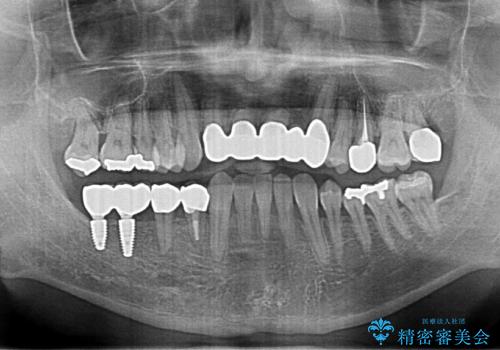

前歯の部分矯正を行い受け口を改善しました。

奥歯まで動かそうとすると顎の手術の適応になってしまうため、奥歯はそのままにして前歯のかみ合わせを改善しました。

また、奥歯はインプラント治療を行い、矯正で下の前歯を後ろに下げるのに使用しています。

時間はかかりましたがしっかり治療することができました。

右下のインプラント治療は横浜桜木町歯科院長大元先生にお願いしています。